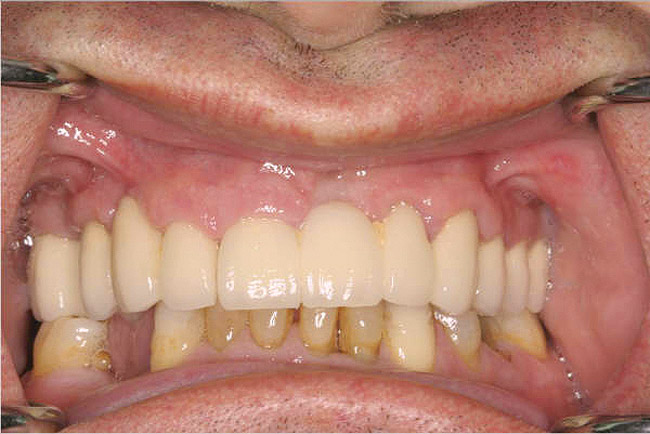

Figure 1  The crown height is measured from the alveolar crest to the occlusal table.

Figure 1